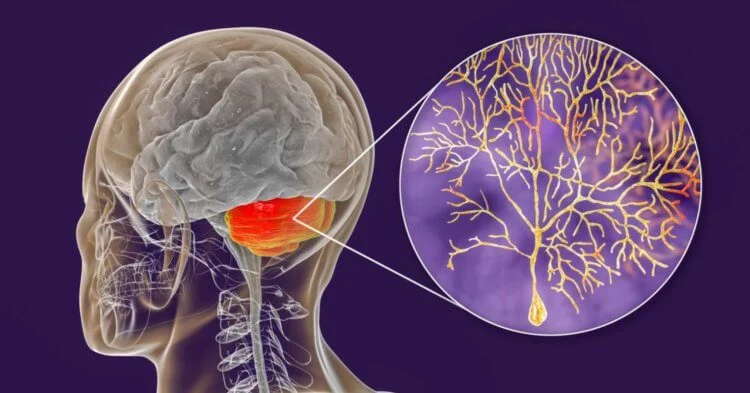

Мозжечок, обучение и клетки Пуркинье

Отметим, что нейробиологи уже более полувека спорят о том, как именно мозжечок – ключевая часть мозга, участвующая в управлении движениями и обучении – учится на самом деле. Ведущая теория предполагала, что обучающие сигналы передаются по восходящим волокнам к коре мозжечка, вызывая долговременные изменения в клетках Пуркинье – основным выходным клеткам мозжечка.

Клетки Пуркинье – грушевидные нейроны коры мозжечка, одни из крупнейших в мозгу.

Однако окончательных доказательств «гипотезы о лазящих волокнах» не было, хотя некоторые исследования предполагали, что изменения в выработке клеток Пуркинье сами по себе, без участия лазящих волокон, могут способствовать обучению.

Поразительно, но результаты нового исследования предоставили убедительные доказательства тому, что лазящие волокна на самом деле обеспечивают необходимые обучающие сигналы для обучения мозжечка. Используя оптогенетику, при которой клетками управляют с помощью света, а также задачи обучения, выполняемые мышами, исследователи смогли продемонстрировать ключевую роль лазящих волокон в этом процессе. Более того, активность лазящих волокон попросту необходима и даже достаточна для формы ассоциативного обучения. Но при чем тут «зомби-нейроны»?